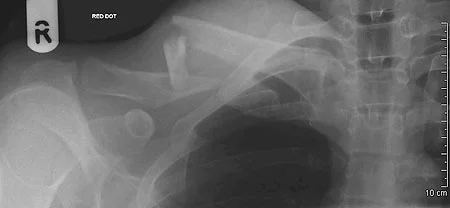

Clavicle Fracture

- Sites:

- Lateral thirds,

- Middle thirds, common (why?)

- Medial thirds

Its weakest point. The lateral fragment is depressed by the weight of the arm against trapezius, thus the shoulder droops, it is pulled medially forward by adductor function of pectoralis major causing the bone fragments to override.